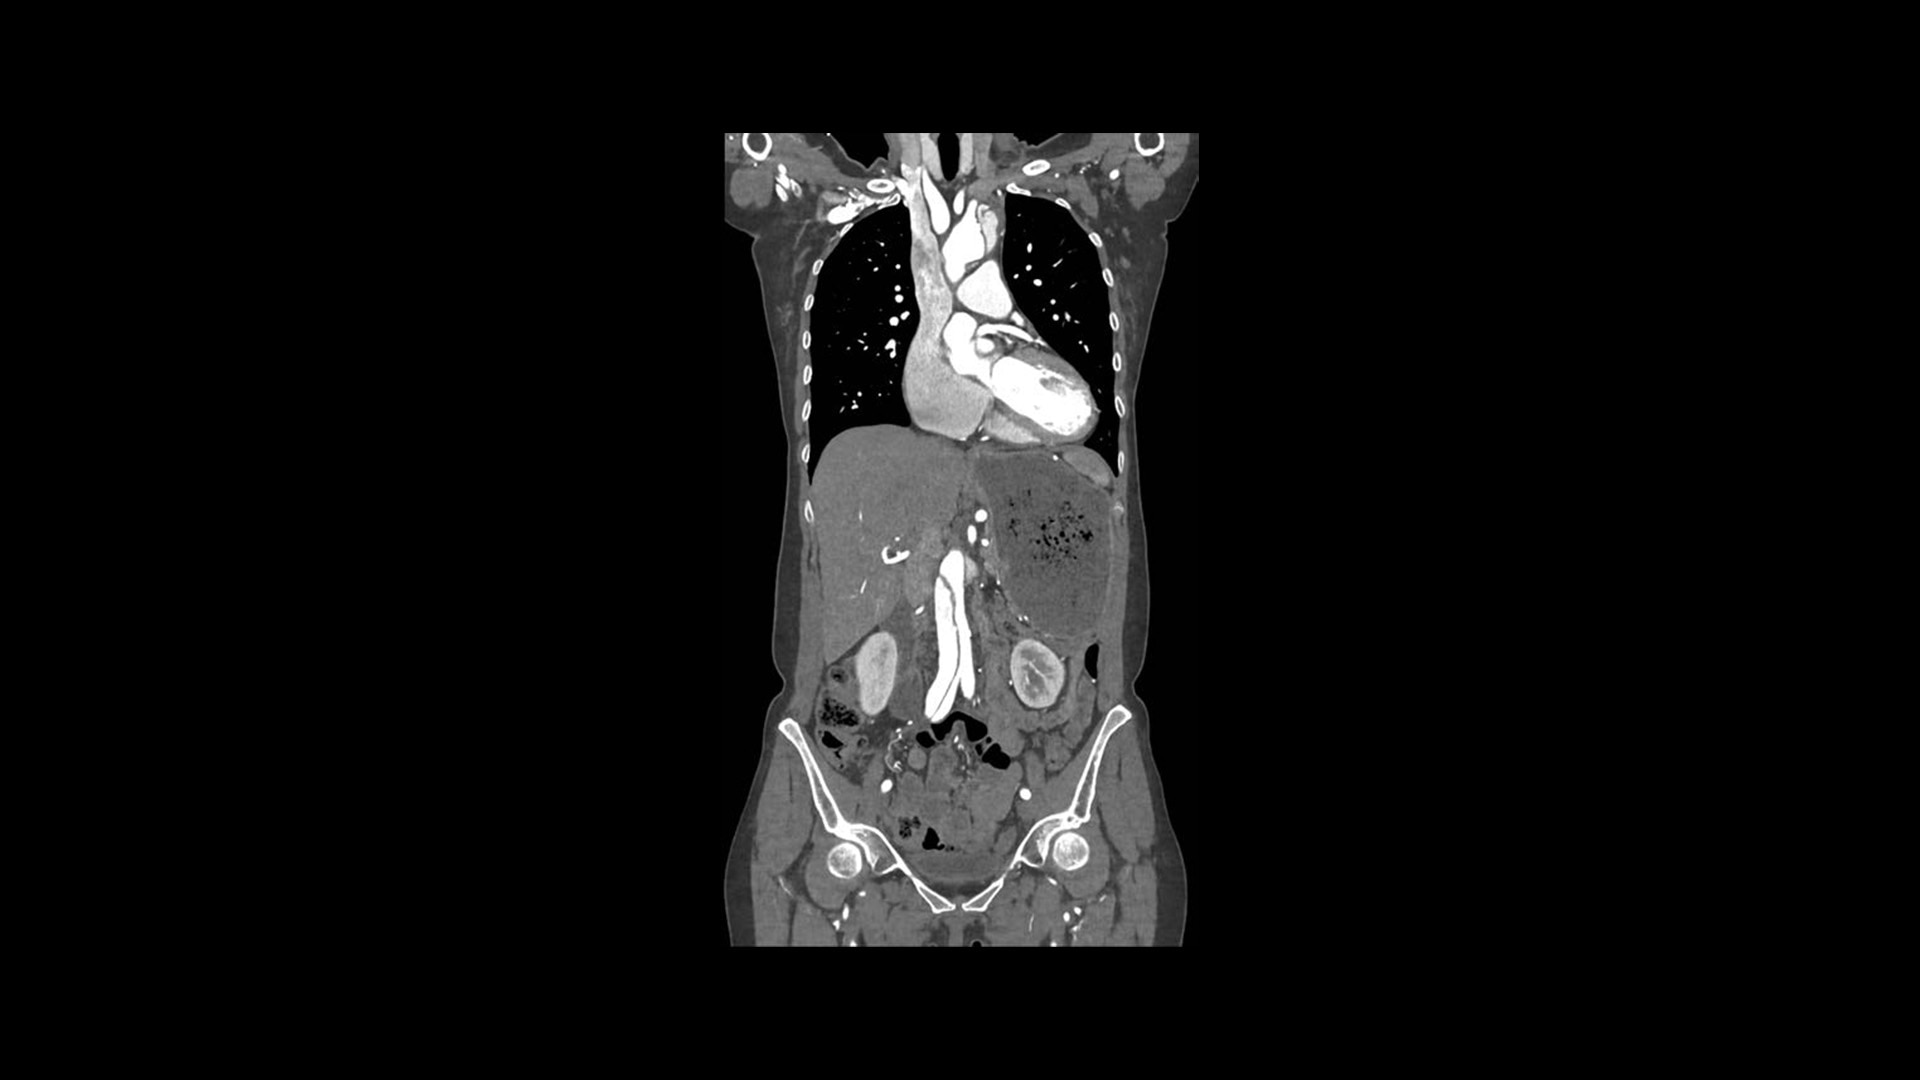

Introducing the new Revolution™ Ascend Platform, our latest CT offering designed to efficiently match your imaging demands. Whether you require a highly efficient system with 20 mm of coverage for routine scanning or a more advanced system with 40 mm of coverage that improves low contrast detectability, you can choose exactly what you need. Since the Revolution Ascend Platform is scalable, you can invest in the CT you need today and take comfort in knowing that it’s ready for tomorrow.

It's time to get ahead in CT. Way ahead.

As the demand for CT procedures continues to increase, you need to image a larger number of patients in a shorter amount of time. You also need CT technology that can keep up. Not just for the routine patients you have today, but also for the challenging patients you’ll have tomorrow. The need for efficiency to stay ahead has never been greater.